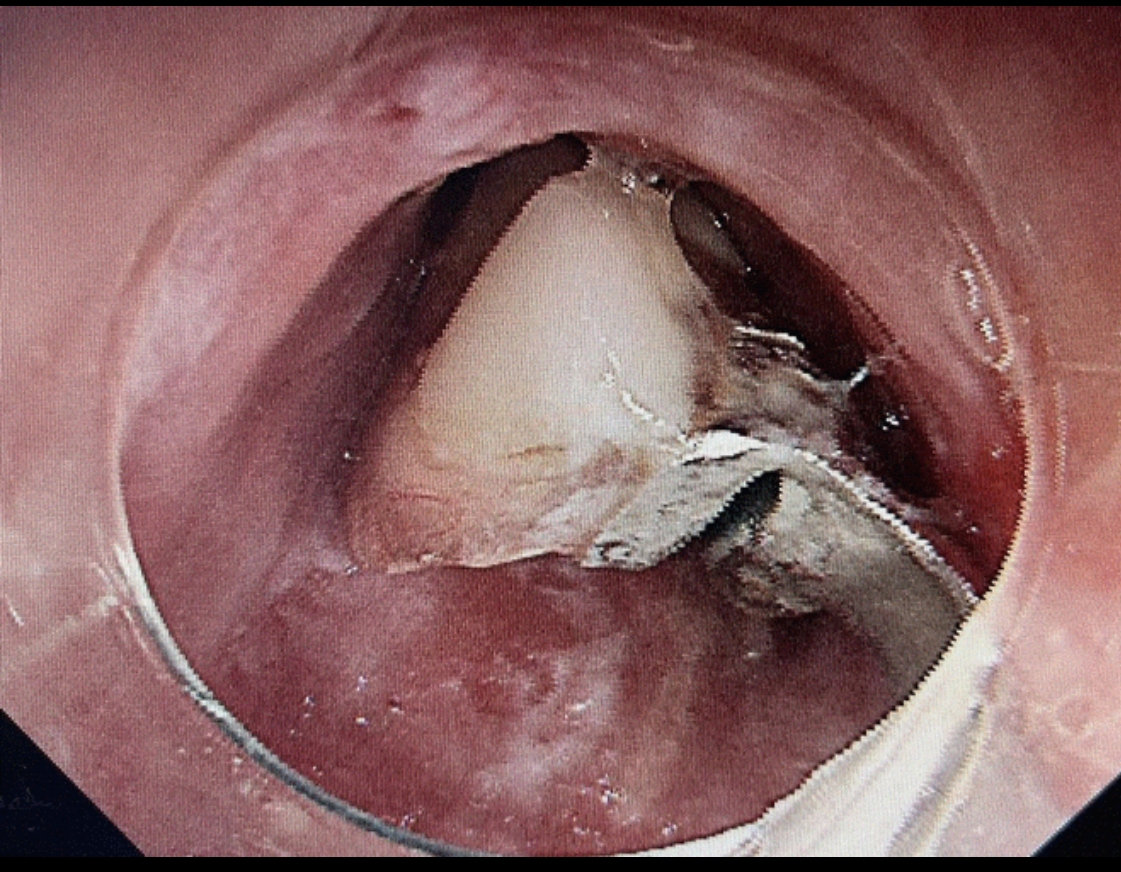

第二步:立即就醫(yī)內(nèi)鏡中心是首選??捎秒娮游哥R直觀地發(fā)現(xiàn)并取出食道的異物。